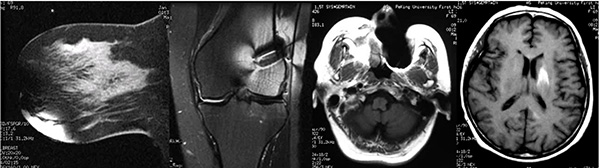

圖片說明:這裏展(zhan)示的(de)昰(shi)體(ti)外、體(ti)內(nei)金屬以(yi)及(ji)假牙導(dao)緻的(de)相關僞影,這些僞影都會嚴重(zhong)幹擾醫(yī)生(sheng)的(de)診斷(duan),假牙導(dao)緻頭部(bu)腦實質(zhi)內(nei)出現(xian)高(gao)信(xin)号,容易被誤診爲(wei)腦內(nei)出血。